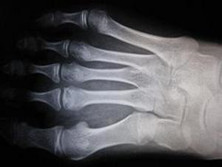

这是非常常见的,通常是由于第一跖骨位置异引起的。偶尔的创伤也是一个原因,因为踝关...

X线平片